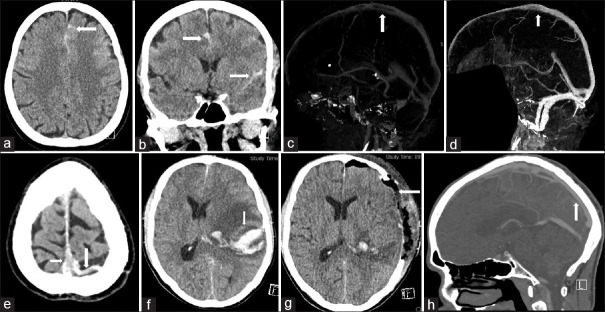

Objectives: Cerebral venous thrombosis (CVT) is a rare type of stroke. Functional outcome (FOC) in CVT can be affected by different factors, and recanalization is an important determinant. This study aimed to identify the FOC predictors including recanalization in patients with CVT.

Methods: This retrospective study reviewed electronic charts of patients with CVT admitted to the King Fahd Hospital of the University, a teaching and referral hospital between January 2012 and March 2023. Demographic and other clinicoradiological characteristics were noted. Factors affecting FOC were investigated using the Chi-square test, odds ratios (ORs), and 95% confidence interval (CI).

Results: Out of 64 patients, 78% achieved good FOC. Age was significantly higher in patients having poor FOC as compared to those having good FOC (P ≤ 0.001). Women had more likelihood to be functionally independent as compared to men (OR = 1.35, 95% CI = 1.01-1.80, P = 0.02). Altered consciousness (OR = 2.94, 95% CI = 1.23-6.99, P = 0.01), venous hemorrhagic infarction (OR = 3.26, 95% CI = 1.36-7.82, P = 0.008), and nonrecanalization (OR = 1.44, 95% CI = 0.97-2.14, P = 0.02) were significantly associated with poor FOC. Hereditary thrombophilia (OR = 0.60, 95% CI = 0.31-1.12, P = 0.03) and infections (OR = 0.59, 95% CI = 0.31-1.12, P = 0.01) were associated with less likelihood of good FOC. Age ≥50 years (P = 0.01) and illness of more than 1-month duration (P = 0.01) were associated with nonrecanalization.

Conclusion: Older age, male sex, presence of venous hemorrhagic infarction, and nonrecanalization can predict poor FOC in CVT. The recanalization process can be affected by late presentation, and the plausible reason could be a delay in therapeutic anticoagulation. Further prospective and multicenter studies are needed to determine the predictors of FOC and to understand the process of recanalization in CVT.